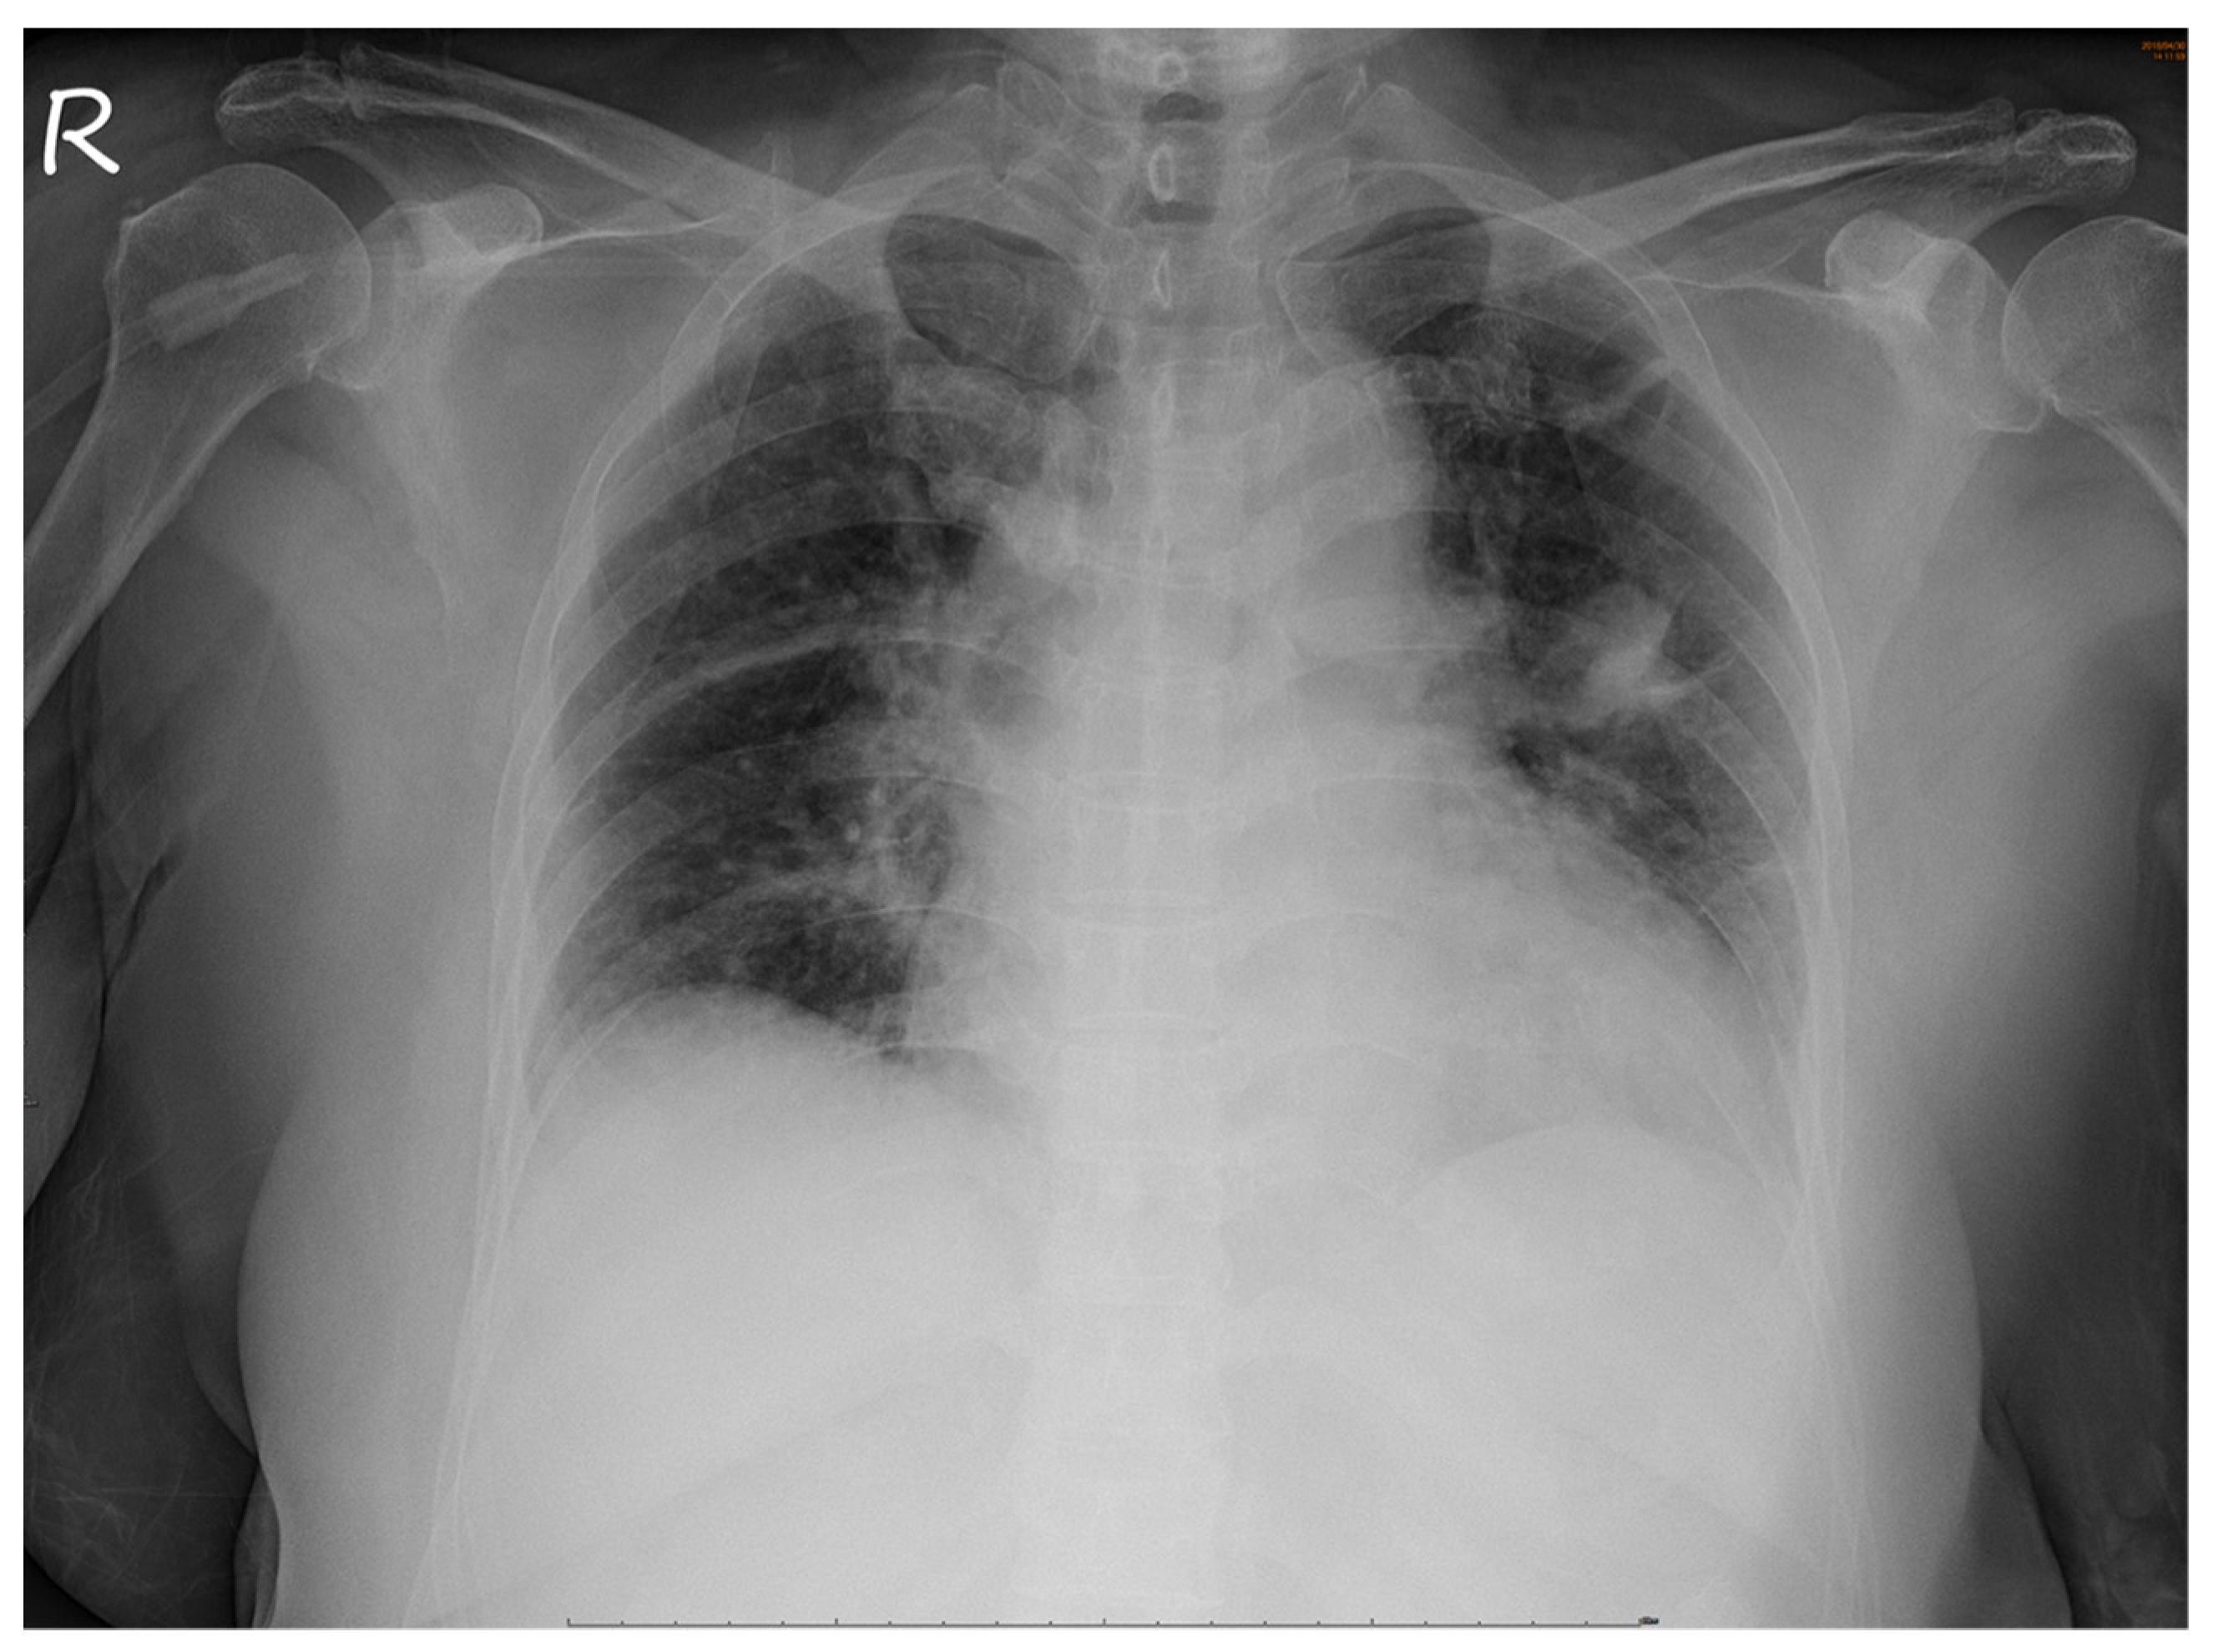

No abnormalities were noted in the right eye. Serological tests for infection, autoimmune diseases, and tumor markers were negative. However, chest radiography revealed a non-homogenous opacity in the superior lobe of the left lung (Figure 4).

Figure 4.

Chest radiograph. A non-homogenous patch is seen in the superior lobe of the left lung.